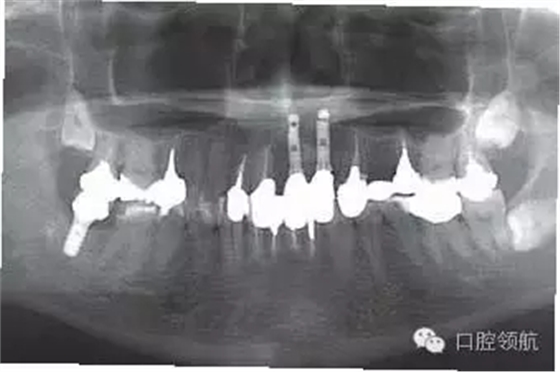

上述的患者具有較高的笑線,所以不影響美學效果(圖4、圖5)。近年,適合于牙齦色的瓷粉和聚合樹脂應用于臨床,是較為可行的應對方法。

圖4 上部修復體戴入口內后,牙列和口唇的關系,由于笑線較高的原因沒有影響美學效果。

圖5 上部修復完成后的全景X線片。